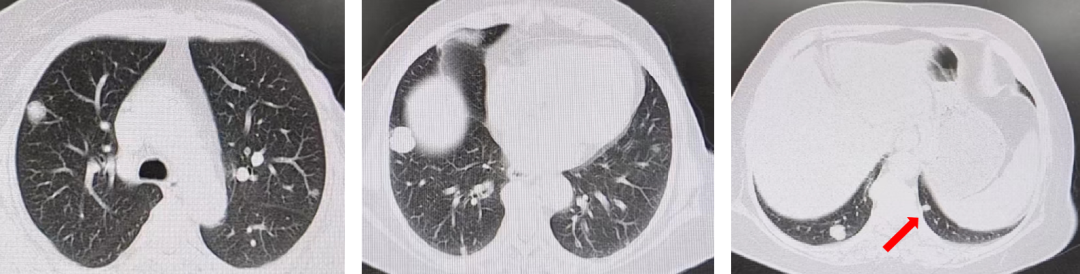

CT引导下肺结节穿刺活检(2021-02-18):坏死组织中可见异型腺体,考虑腺癌。免疫组化结果(2021-02-24):AE1/AE3(+),TTF-1(-),CDX2(+),NapsinA(-),CK20(+)。

Ki-67(阳性细胞数60%),腺癌,考虑胃肠源性。

KRAS、NRAS、BRAF基因检测:KRAS 2号外显子G12X突变。MLH1(+),PMS2(+),MSH2(+),MSH6(+),HER2(0)。